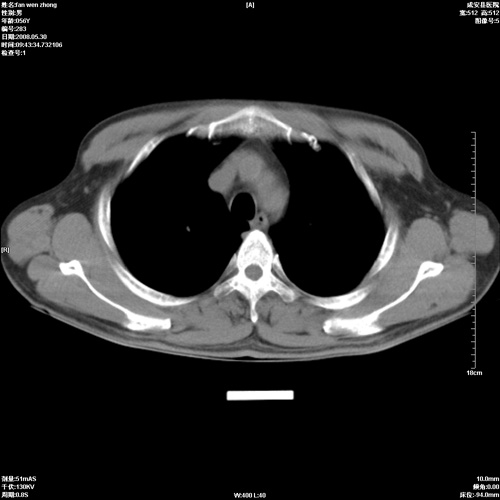

病人 男 56岁 一周前高热,体温达39-40度,经抗炎治疗后,体温渐降,达37,5-38度,轻微咳嗽,胸部不适 查白细胞为1.3万 行ct检查,请分析。

该病例虽然血象高,一周前高热。警惕!不能除外右肺周围型肺癌并肺内转移。一定要作胸穿、病理检查,以便确诊。或继续抗炎治疗后复查ct。

双肺内可见多发结节状病灶,并见小空洞,病人高热,白血球增高,应该是典型的迁徙性肺脓肿(多为金黄色葡萄球菌感染)。查一下口腔等其它部位有无感染灶。

双肺内可见多发结节状病灶,并见小空洞,病人高热,白血球增高,应该是典型的迁徙性肺脓肿(多为金黄色葡萄球菌感染)。建议治疗后复查.